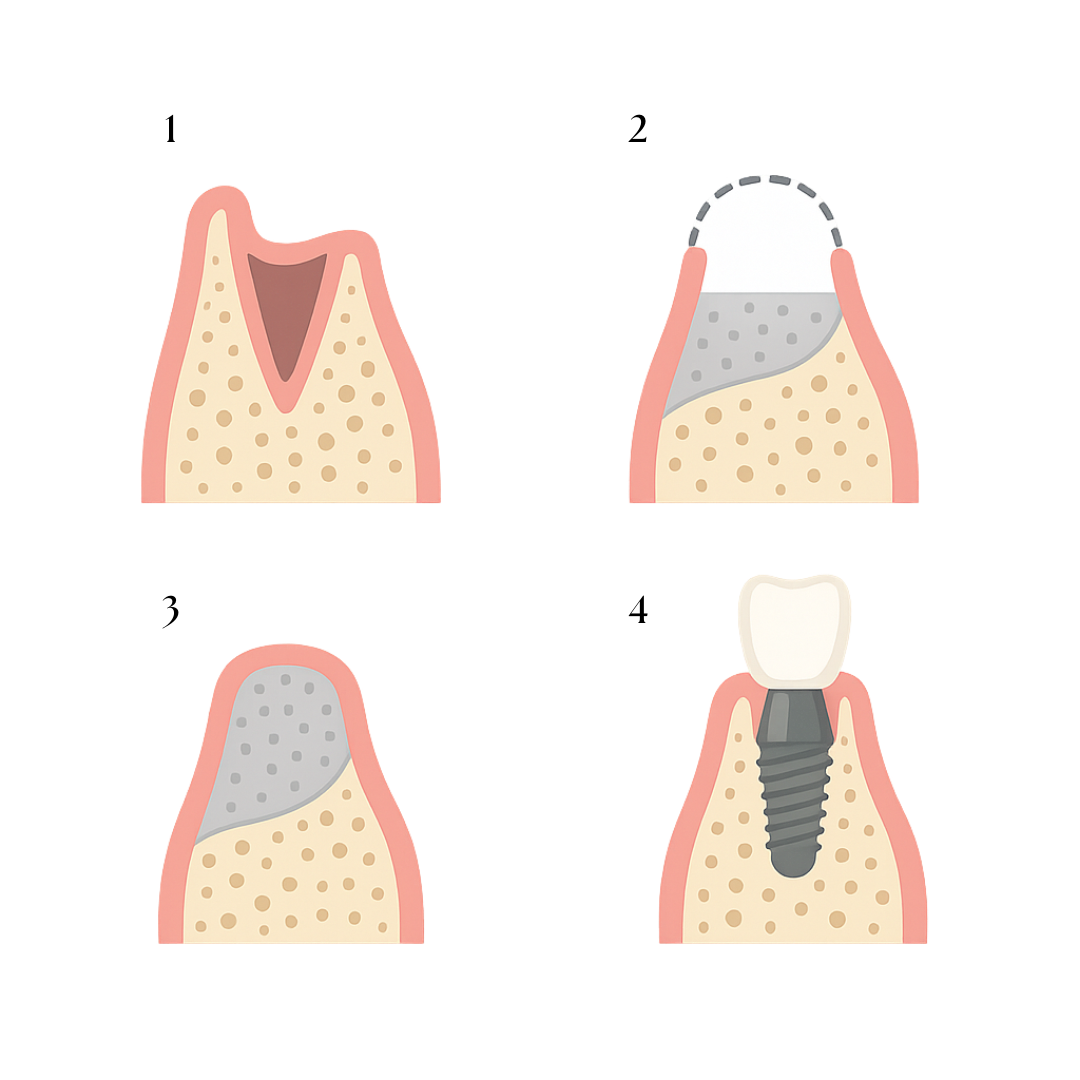

Bone regeneration

Through safe and personalised procedures, we create the necessary foundation to place dental implants where it was previously impossible. We thoroughly study each case so you can smile again with full confidence and functionality.

Bone regeneration

When there isn’t enough bone to place an implant, we use advanced regeneration techniques to recover lost volume and ensure a successful treatment.